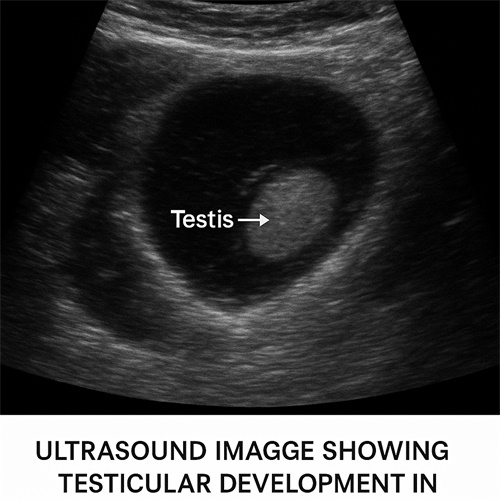

Testicular Development in Breeder Pigeons

For breeder pigeons, monitoring testicular development is crucial for assessing their breeding potential. As male pigeons reach sexual maturity, the testes undergo physical changes that can be observed through ultrasound. By using the BXL-DB20 OPU Veterinary ultrasound, breeders can monitor the development of the testes in male pigeons and make informed decisions about when the birds are ready for breeding.

Testicular size and structure can be evaluated, providing insight into the reproductive health of the pigeon. Early detection of potential problems, such as testicular atrophy or abnormal development, allows for prompt intervention, ensuring the overall health and productivity of the breeding stock.

Understanding the timing of testicular development also helps manage the breeding cycle more effectively. Ultrasound allows breeders to pinpoint the optimal time for pairing male and female pigeons, maximizing the chances of successful breeding and reducing the risk of infertility or unwanted breeding behaviors.